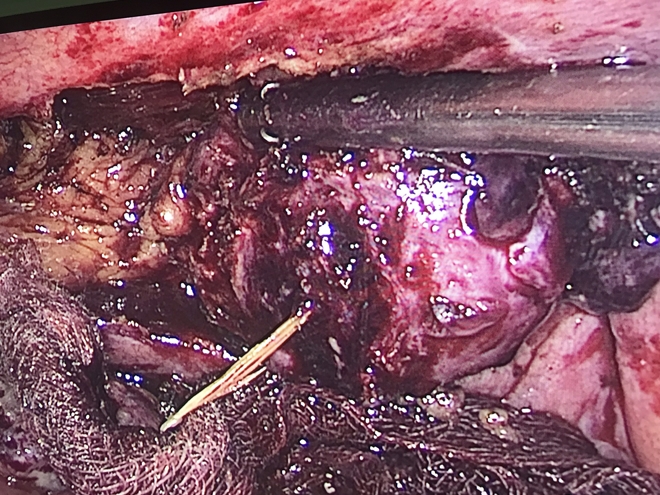

Hình ảnh phẫu thuật.

Bệnh nhân có chỉ định phẫu thuật nội soi cấp cứu, Ê-kíp phẫu thuật do các bác sĩ Khoa Ngoại Tổng hợp và Khoa Phẫu thuật – Gây mê hồi sức tiến hành bóc tách khối viêm ở thành bụng, hố chậu trái có khối viêm dầy kích thước 3x4cm được mạc nối lớn bám.

Phẫu tích khối viêm ở thành bụng, cắt mạc nối lớn lấy một dị vật xương cá dài 3cm. Cắt khối viêm và mạc nối lớn làm giải phẫu bệnh. Phẫu thuật diễn ra thành công sau 1 giờ.